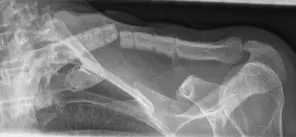

Abbildung: Zweite Episode einer Re-Fraktur bei einer jungen Patientin. Daher Revision mit langer Platte und zudem Einsetzen eines Beckenkammspans (rot markiert) post-OP und das Ausheilungsergebnis 1 Jahr nach der OP